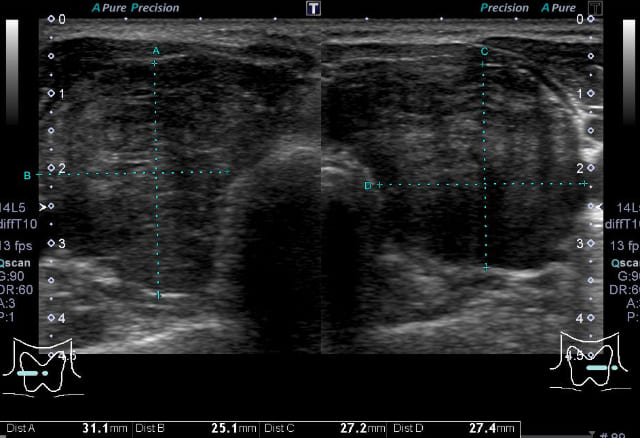

甲状腺超音波(エコー)検査では、甲状腺は基本的には全体的に大きくなり、内部は粗くみえることが多いです。臨床診断は、甲状腺の全体的な腫大に加えて、TgAbまたはTPOAb陽性で行います。甲状腺機能が正常であれば治療の必要はありません。機能が低下している場合には飲み薬(チラーヂンS®、レボチロキシン®)によって甲状腺ホルモンの補充を行います。服用は一日一回です。(吸収の安定性からは空腹時の服用がよく、また金属系製剤と同時服用は避ける必要があります)